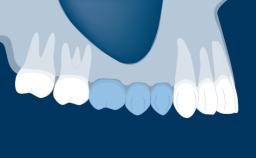

Fixed and removable prosthodontic implant therapy for restoration of the edentulous maxilla is both complex and challenging. Careful assessment and planning is needed in each individual case to explore whether a fixed or a removable solution will be the more suitable to satisfy the patient’s preference for optimal esthetics, phonetics, comfort and function. This Learning Pathway explores the prosthodontically driven treatment planning based on structured assessment, considered diagnosis and practical application in clinical case examples.

• identify decisive factors based on structured assessment and treatment planning